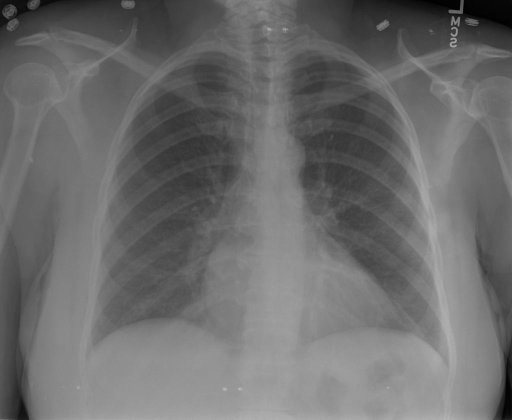

- (1)准备[诊疗报告(中文)](./data/Xray/openi-zh.json)和[X光影像](https://pan.baidu.com/s/13GBsDMKf6xBZBSHpoWH_EA?pwd=k9sh)在`data/Xray`文件夹下; - (2)开始训练: ```bash # 设置CUDA变量,主要是为了解决有时候直接训练而出现无法正确加载到显卡问题 export CUDA_VISIBLE_DEVICES=0,1,2,3 # 开始训练 bash finetune_XrayGLM.sh ``` 这里的复现过程非常简单,主要是很多过程我们都为大家准备好了,大家可以随时复现一个自己的`XrayGLM`。 ### 4.模型训练(通用) - [【官方视频教程】XrayGLM微调实践](https://www.bilibili.com/video/BV1Yh4y147gx/) - [复旦大学《大语言模型理论与实践》](https://intro-llm.github.io/) ## 效果展示 *以下效果来自于**低质量**的数据训练和权重 影像诊断: |X光影像|诊疗报告(医生)|XrayGLM| |:-|:-|:-| |![](./data/Xray/2_1.png)|根据X射线图像,心脏大小正常,肺部看起来很清晰。已经排除了肺炎、积液、水肿、气胸、腺病、结节或肿块的存在。该发现表明一切正常。换句话说,总体印象是胸部正常。|X光片显示,心脏大小正常。肺部没有气胸或胸腔积液的证据。骨骼结构看起来没有任何异常。总的来说,X光片表明没有发现急性心肺疾病的迹象。| |![](./data/Xray/2882_1.png)|X光图片显示没有扭曲的区域、可疑的骨质不透明度或胸腺积液。心脏大小轻微增大,但非常稳定。此外,没有气胸的证据,肺野也正常。总体来说,X光片显示没有急性心脏异常,但要注意轻微的心脏扩大。|X光片显示,心脏大小正常。肺部和纵隔轮廓清晰,没有气胸或胸腔积液的证据。骨骼结构完整,没有任何急性异常。| |![](./data/Xray/2577_1.png)|心影形态在正常范围内。没有急性骨质异常。有可能出现没有明显的吸水或肺实质状况的线索。没有大面积积液或气胸。有可能怀疑其有误吸或肺实质问题。为了确诊和治疗,可能需要进行适当的影像学随访。|心脏大小正常,肺部和纵隔轮廓清晰。没有急性异常或活动受限的证据。没有任何明显的气胸、胸腔积液或肺不张的迹象。此外,也没有发现任何局灶性骨质异常或其他急性疾病。| 多轮对话: |X光影像|诊疗报告(医生)| |:-|:-| |![](./data/Xray/861_1.png)|右侧主动脉突出观察到。心脏大小正常。胸部未发现明显的肺气肿、胸膜积液或可疑的肺部病变。报告指出已知右侧主动脉情况正常。| ```bash >> X光影像路径:./data/Xray/861_1.png >> 用户:这是一张什么图? >> XrayGLM:这张图片显示的是一张肺部检查的X光片。 >> 用户:请描述这张胸部X光片的诊断结果 >> XrayGLM:心脏大小正常,肺部清晰。没有急性心肺疾病的证据。 >> 用户:是否存在肺气肿? >> XrayGLM:没有肺气肿。心脏大小正常,肺部清晰。没有发现急性心肺疾病的证据。 >> 用户:平时饮食该注意什么? >> XrayGLM:饮食应该健康,均衡。建议增加蛋白质的摄入量,因为蛋白质有助于维持肌肉和骨骼的健康。多食用蔬菜、水果、全谷物以及健康的脂肪来源如橄榄油、鱼类等可以帮助获得足够的维生素和矿物质。此外,避免过度饮酒或吸烟,这些习惯可能会对心脏健康产生负面影响。 ``` ## 未来展望 1. 模型的能力更多来源于数据的支持,`OpenI-zh`作为微调数据集,其数据量足以支持研究,在更广泛的任务和性能表现上,我们认为**在大规模数据集上预训练并在高质量少量数据集上微调是一种可行的方案**; 2. 普遍意义的理解上,视觉多模态模型=视觉模型+语言模型。除了需要关注视觉模型信息与语言模型输出的搭配外,还需要**额外关注到语言模型的加强,在人机的对话中,尤其是医疗语言模型的问答上,除了专业的医疗问题回答,带有人文情怀的有温度的回答更应该是我们追寻的目标**。 3. **高精度的模型永远打不过大参数的模型**,如果在6B模型和13B模型上选择微调,请在资源充足情况下选择13B的大参数模型; ## 项目致谢 1. [VisualGLM-6B](https://github.com/THUDM/VisualGLM-6B)为我们提供了基础的代码参考和实现; 2. [MiniGPT-4](https://github.com/Vision-CAIR/MiniGPT-4)为我们这个项目提供了研发思路; 3. ChatGPT生成了高质量的中文版X光检查报告以支持XrayGLM训练; 4. [gpt_academic](https://github.com/binary-husky/gpt_academic)为文档翻译提供了多线程加速; 5. [MedCLIP](https://github.com/RyanWangZf/MedCLIP) 、[BLIP2](https://huggingface.co/docs/transformers/main/model_doc/blip-2) 、[XrayGPT](https://github.com/mbzuai-oryx/XrayGPT) 等工作也有重大的参考意义; ![](./assets/images/mpu.png) 这项工作由[澳门理工大学应用科学学院](https://www.mpu.edu.mo/esca/zh/index.php)硕士生[王荣胜](https://github.com/WangRongsheng) 、[段耀菲](https://github.com/IsBaSO4) 、[李俊蓉](https://github.com/lijunrong0815)完成,指导老师为檀韬副教授、[彭祥佑](http://www.patrickpang.net/)老师。 *特别鸣谢:[USTC-PhD Yongle Luo](https://github.com/kaixindelele) 提供了有3000美金的OpenAI账号,帮助我们完成大量的X光报告翻译工作 ## 免责声明 本项目相关资源仅供学术研究之用,严禁用于商业用途。使用涉及第三方代码的部分时,请严格遵循相应的开源协议。模型生成的内容受模型计算、随机性和量化精度损失等因素影响,本项目无法对其准确性作出保证。即使本项目模型输出符合医学事实,也不能被用作实际医学诊断的依据。对于模型输出的任何内容,本项目不承担任何法律责任,亦不对因使用相关资源和输出结果而可能产生的任何损失承担责任。 ## 项目引用 如果你使用了本项目的模型,数据或者代码,请声明引用: ```bash @misc{wang2023XrayGLM, title={XrayGLM: The first Chinese Medical Multimodal Model that Chest Radiographs Summarization}, author={Rongsheng Wang, Yaofei Duan, Junrong Li, Patrick Pang and Tao Tan}, year={2023}, publisher = {GitHub}, journal = {GitHub repository}, howpublished = {\url{https://github.com/WangRongsheng/XrayGLM}}, } ``` 我们的工作被[Evaluating Large Language Models for Radiology Natural Language Processing](https://arxiv.org/abs/2307.13693)引用,希望大家去关注一下相关的工作! ## 使用许可 此存储库遵循[CC BY-NC-SA](https://creativecommons.org/licenses/by-nc-sa/4.0/) ,请参阅许可条款。